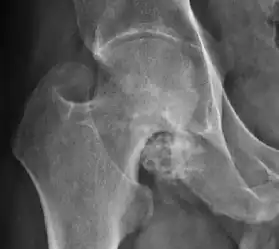

Plain radiography allows us to categorize the hip as normal or dysplastic or with impingement signs (pincer, cam, or a combination of both). Besides these, pathologic processes like osteoarthritis, inflammatory diseases, infection, or tumors can also be identified (Figure 1).[1]

Figure 1.

-

Radiography in normal hip -

X-ray in pincer impingement type of hip dysplasia -

X-ray of cam -

Hip in osteoarthritis -

Septic arthritis

There are other pathological conditions that can affect the hip joint and radiographs help to make the appropriate diagnosis. Acute bacterial septic arthritis can be diagnosed by radiographs when a fast regional osteoporosis and destructive monoarticular process develops (Figure 1(f)). In case of tuberculous or brucella arthritis it is manifested as a slow progressive process, and diagnosis may be delayed.[1]

Synovial chondromatosis can be confidently diagnosed by X-ray when calcified cartilaginous chondromas are seen. However, other synovial proliferative processes, such as pigmented villonodular synovitis, require MRI for accurate diagnosis, although noncalcified synovitis can be suspected in radiographs by indirect signs, such as soft tissue swelling and/or erosions in the femoral head, femoral neck, or acetabulum (Figure 7).[1]